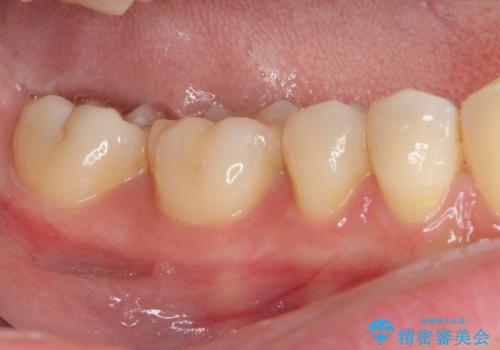

セラミックインレーを装着したことで、とても自然な仕上がりとなりました。

患者様も大きく口を開けても気にならなくなった、大変喜んでくださいました。